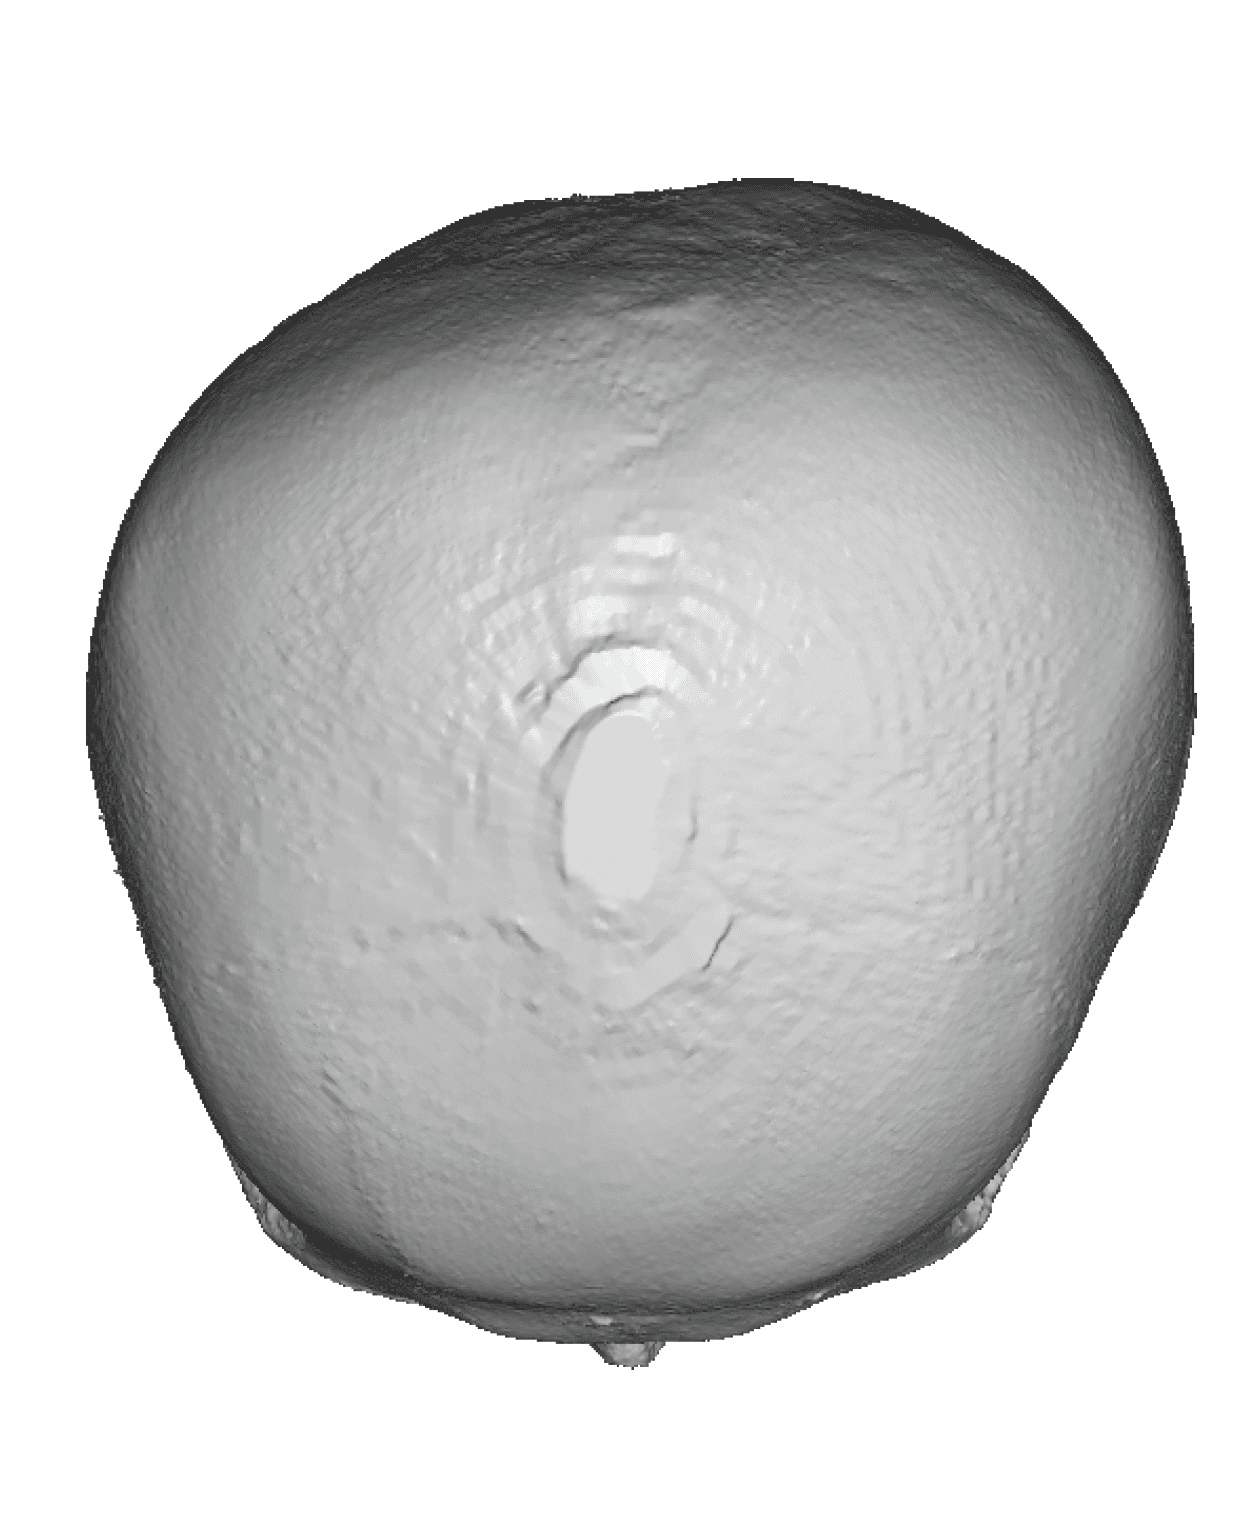

Patient 35

Severe narrowing skull deformity from prior sagittal craniosynostosis repair as an adult.

Complete replacement of entire skull by a custom implant with temporal fat injections.

Severe narrowing skull deformity from prior sagittal craniosynostosis repair as an adult.

Complete replacement of entire skull by a custom implant with temporal fat injections.